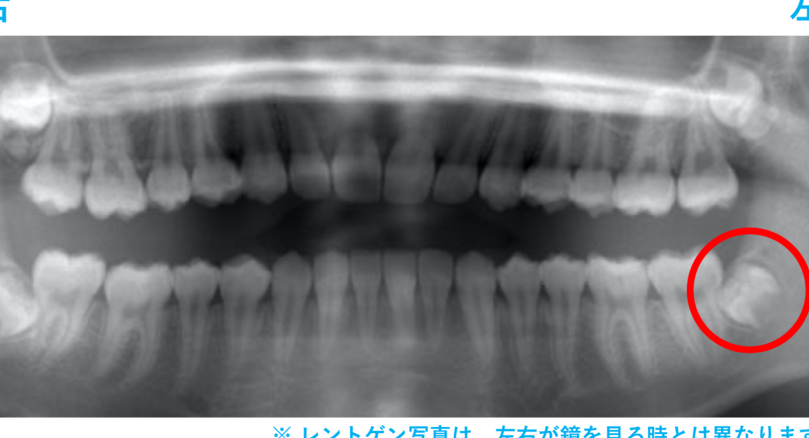

- 歯のスペース:顎の大きさにより親知らずがうまく生えない場合も

- 生え始めのタイミング: 親知らずが完全に生える前に抜歯することが望ましいです。この時期は通常、18歳から25歳の間に訪れます。